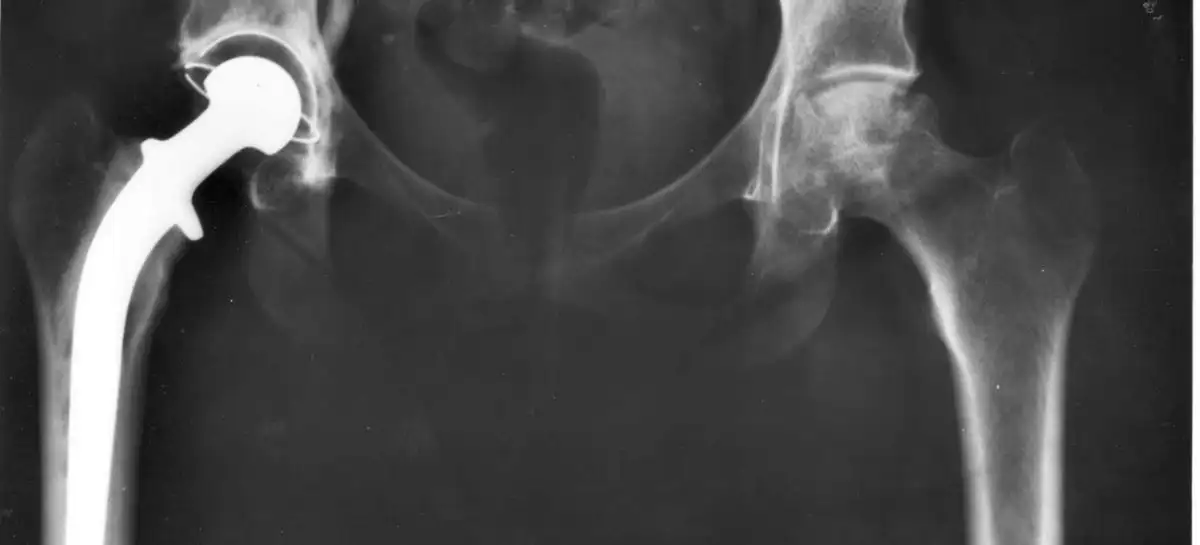

استبدال مفصل الورك

استبدال مفصل الورك: دليل شامل مقدمة استبدال مفصل الورك، أو جراحة استبدال الورك، هي عملية جراحية يتم فيها استبدال الجزء التالف أو المصاب من مفصل الورك بجزء صناعي. تُعتبر هذه الجراحة من أكثر العمليات الجراحية نجاحًا في مجال جراحة العظام، حيث تساعد المرضى على استعادة الحركة وتخفيف الألم الناتج عن التهاب المفاصل أو الإصابات الأخرى.…